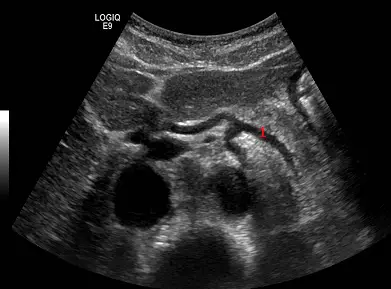

當超音波探頭以橫向方式掃描腹部時,出現如下圖海鷗影像( seagull sign ), 編號 1 為:

本題測驗上腹部超音波(Abdominal Ultrasound)的經典解剖影像特徵。在橫切面(Transverse plane)掃描腹主動脈時,常藉由特定血管的分支型態來定位解剖構造,其中最著名的即為「海鷗影像」(Seagull sign),用以辨識腹腔動脈幹(Celiac trunk)及其主要分支。

- 影像為上腹部橫切面超音波(Transverse view)。依據標準超音波方向,螢幕左側代表病患的右側,螢幕右側代表病患的左側。

- 畫面下方偏中央的巨大、無回音(黑底)圓形構造為腹主動脈(Abdominal aorta)。

- 腹主動脈前方分支出一條短的主幹,即為腹腔動脈幹(Celiac trunk),這構成了海鷗的「身體」。

- 腹腔動脈幹隨後分為兩條主要分支:

- 往畫面左側(病患右側)延伸的分支為總肝動脈(Common hepatic artery),這構成了海鷗的「右翼」。

- 往畫面右側(病患左側)延伸的分支為脾動脈(Splenic artery),這構成了海鷗的「左翼」。

- 圖中紅色數字「1」所指的血管,正位於畫面右側並朝病患左方(脾臟方向)延伸。